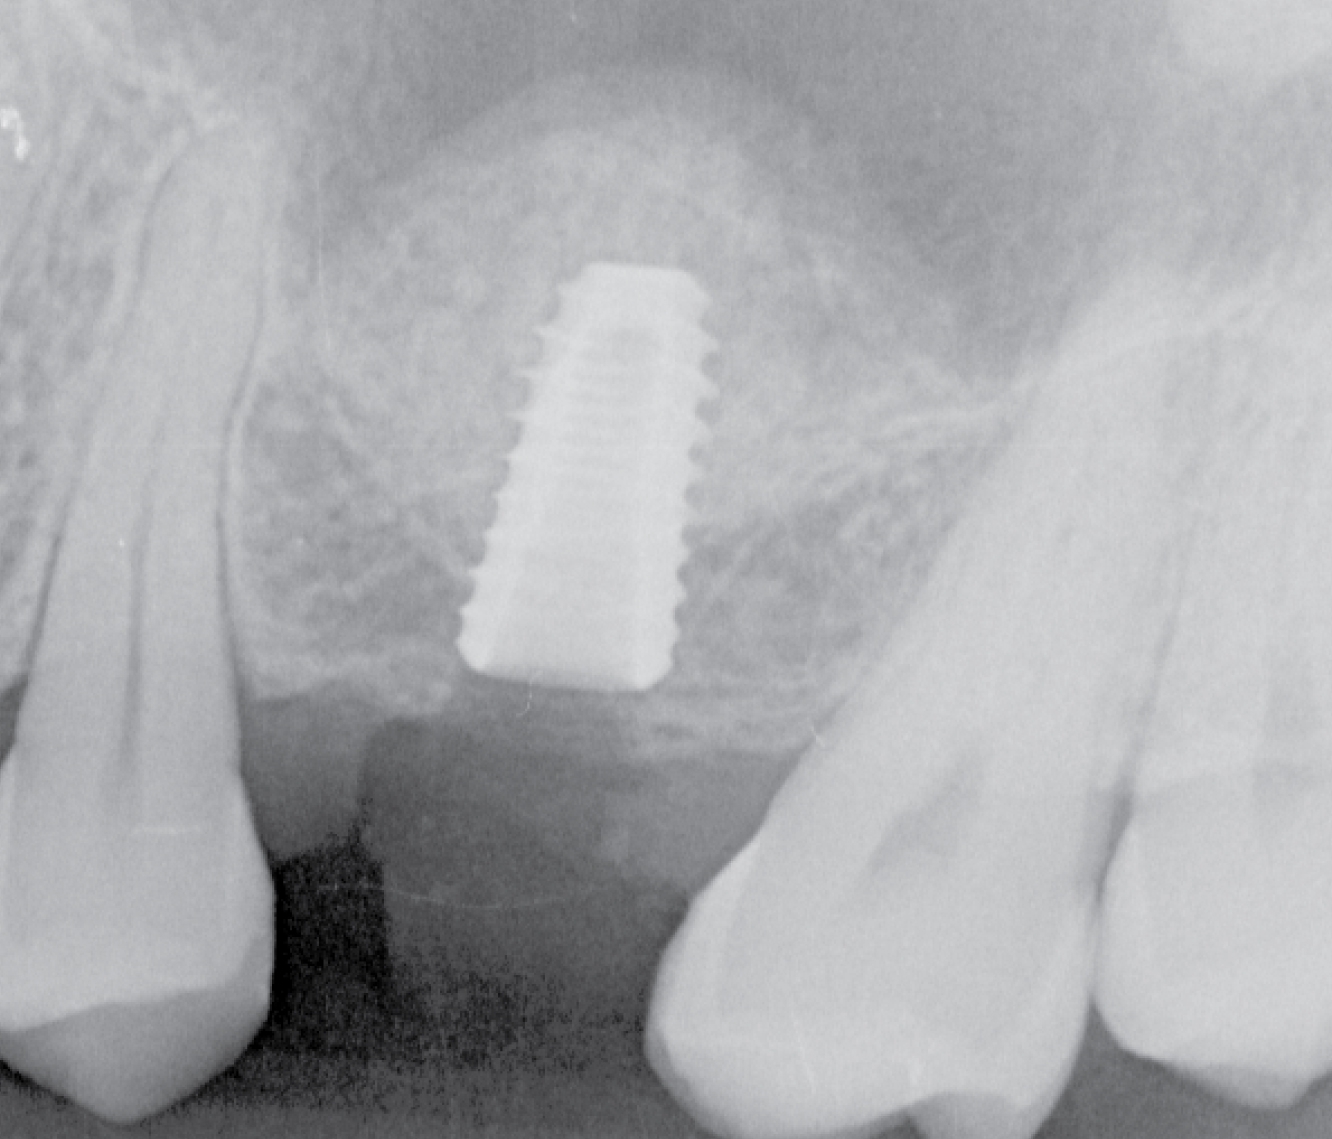

Director’s Clinical Cases

Director’s Clinical Cases